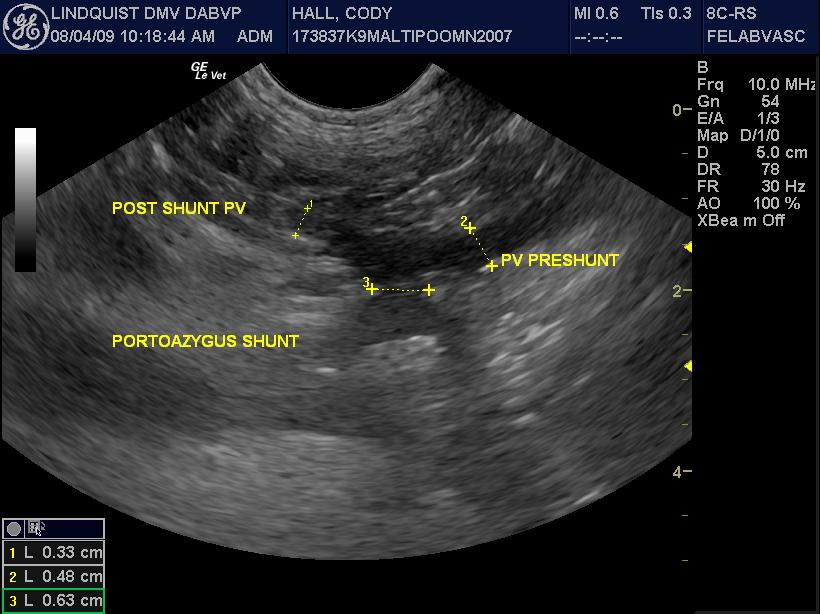

A 2-year-old MN Malti-poo was presented for recheck examination after being evaluated at an emergency facility for anorexia, diarrhea, and a pruritic face. Abnormalities on blood work at the emergency facility were elevated ALT activity and bilirubinuria. Physical examination was unremarkable. CBC and blood chemistry showed leukocytosis, neutrophilia, monocytosis, elevated BUN, high BUN/Creatinine ratio, and mild hypocalcemia. Urinalysis was normal. Urine culture yielded no growth.